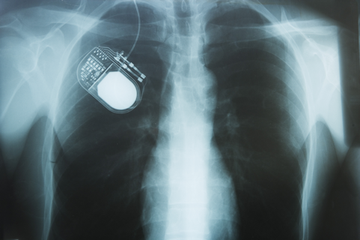

Diagnostic System with Piezo Electric Transformer for Ultrasound

Secondary Coils for Magnetic Resonance Imaging

Wireless Charger for Medical Devices